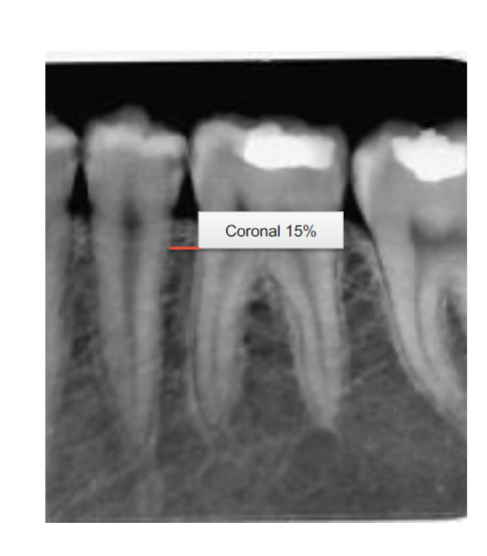

Q

Stage 2 x-ray PD looks like…

19

What stage is this?